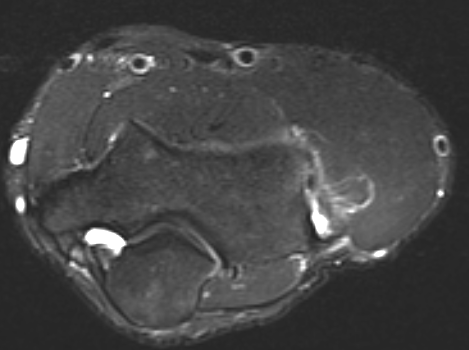

MRI

High grade partial tears of ECRB on lateral eipcondyle

Tendonopathy of the common extensor origin, with thickening and high grade tear partial tear

Tendonopathy of the common extensor origin, with thickening and high grade tear partial tear